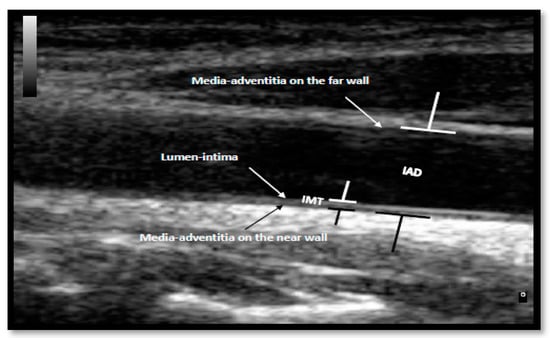

2.2.3. Vascular Structure and Kinetic Measurements

| IMT, mm | 0.0001 ** | ||||

| Median (IQR) | 0.49 (0.18) | 0.556 (0.19) | 0.696 (0.35) | 0.575 (0.25) | |

| IAD, mm | 0.004 ** | ||||

| Mean ± SD | 6.32 ± 0.62 | 6.61 ± 0.68 | 7.03 ± 0.94 | 6.65 ± 0.81 |